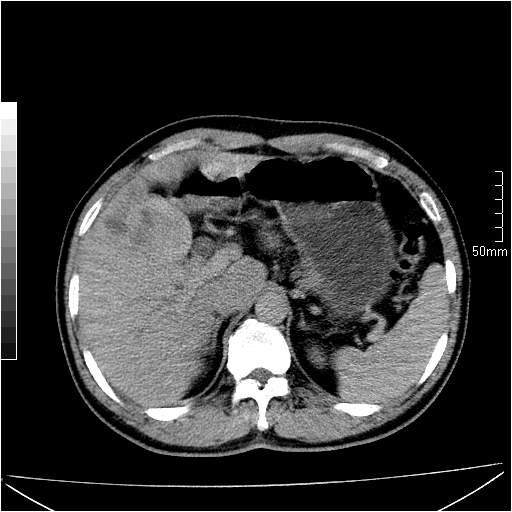

男性,54岁,皮肤黄染,搔痒一周余.b超示肝左叶回声异常.初步诊断1胆总管下段结石2胆囊结石伴慢性胆囊炎请各位战友帮忙看一下肝脏多发低密度如何解释恰当.增强效果不是很好.请大家见谅.

胆总管及肝内胆管扩张,考虑是结石!但,肝内的低密度区增强不明,可能是肝ca,因为肝ca在增强时呈快进快出.另年胆总管扩张原因,可以考虑一下是不是,胆管ca.再次要考虑肝内的低密度是否为海绵状血管瘤所致!

首先,胆总管下端结石梗阻伴肝内胆管扩张可确定。

另外,肝八段低密度占位,呈多灶性,考虑肝脓肿或肝癌可能,(图像质量欠佳)建议进一步检查。

既然做了增强,为什么光提供延时期片子,肝动静脉期肝右叶前下段病灶增强如何?另外胆囊壁增厚,欠规整,内密度不均,与肝右叶病灶分界不清,增强表现怎样?肝内胆管轻度扩张,胆总管扩张,但未见明显结石影,也应提供增强早期图像才好鉴别扩张原因。片子较清,但不够完整,暂考虑1.胆囊癌肝局部浸润,或肝癌胆囊侵犯,2.胆总管下端或胰头钩突部占位。总之本人看不明白,请高手画图指示,先谢了!

由于胆囊窝内结构显示不清,肝脏病灶又邻近胆囊窝首先考虑胆囊癌肝受侵犯。而后因肝脏病灶强化有渐进改变,且相邻胆管扩张,故考虑肝胆管细胞癌待排。

左肝胆管细胞癌。

胆总管下端结石。